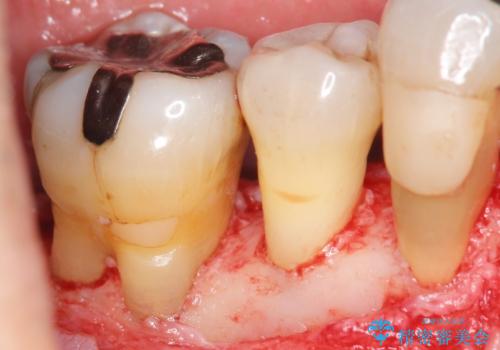

- 全顎的な重度歯周病の患者様です。

骨吸収の進行している右下臼歯部に、再生療法(骨を増やす手術))を行いました。

再生療法から1年後、リエントリー手術により骨の再生を確認し、骨外科処置(骨を平らにして歯周ポケットの根本的な改善を図る処置)を行いました。

埋伏していた親知らず、保存不可能な右下の一番奥の歯(右下7)、状態の悪い犬歯(右下3)は抜歯しております。